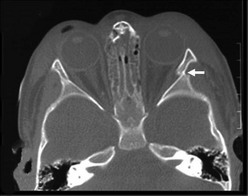

Subdural hemorrhages are classified as acute (<3 days old), subacute (3-10 days old), and chronic (>10 days old). Acute and subacute subdural hemorrhages are not infrequent in infants, and often the result of birth injury or NAT (Fig. 17-4). They usually result from lacerated bridging veins, or from associated contusions hemorrhaging into the subdural space. The superficial cortical veins in small children lack any reinforcement from arachnoidal trabeculae and are susceptible to inertial loading. Subdural hematomas tend to follow the convexities of the brain and cover the entire hemisphere. The cranial CT demonstrates hyperdense crescent-shaped blood collections at the surface of the brain, often associated with mass effect and cortical edema. Occasionally, and particularly when anemia is present, the CT findings of an acute subdural hematoma may have an isodense appearance that belies the actual hemorrhagic character later found at the time of operation.

FIGURE 17-4 Hyperacute subdural bleeding (arrow) is seen on this cranial CT scan of a 9-month-old patient. (Courtesy of Dr Lisa Lowe.)